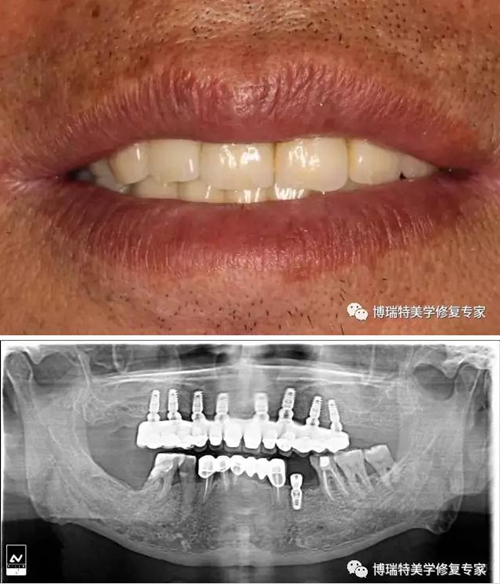

螺絲固位基臺(tái)也稱為復(fù)合基臺(tái),復(fù)合基臺(tái)按基臺(tái)與種植的長(zhǎng)軸關(guān)系主要分為直式復(fù)合基臺(tái)和角度基臺(tái)。由于能夠在一定的角度誤差范圍內(nèi)為相鄰種植體取得共同就位道, 多適用于多單位橋體修復(fù), 除此之外, 復(fù)合基臺(tái)也能用于提升修復(fù)體的安放平臺(tái)。

1.jpg

1,螺絲固位基臺(tái)優(yōu)勢(shì)在于:

1、 簡(jiǎn)化種植手術(shù)過程,擴(kuò)大種植牙的適應(yīng)癥;

2、對(duì)于骨量不足的患者,可采用斜行種植方案來完成修復(fù);

3、把骨水平的修復(fù)方案轉(zhuǎn)移到軟組織水平完成修復(fù),方便后期的操作;

4、方便患者后期的種植牙維護(hù);

5、尤其適合全口無牙頜的種植方案;

按照調(diào)整修復(fù)螺絲方向,可以分為螺絲固位直基臺(tái)與螺絲固位角度基臺(tái),螺絲固位角度基臺(tái)有17°和30°兩種。兩種角度基臺(tái)均有抗旋結(jié)構(gòu)設(shè)計(jì)。

按照穿齦高度,螺絲固位直基臺(tái)有三種穿齦高度:分別為1mm、2mm、3mm。

螺絲固位17°角度基臺(tái)有三種穿齦高度,分別為1-2.5、2-3.5和3-4.5mm。

螺絲固位30°角度基臺(tái)有三種種穿齦高度,分別為1-3.5、2-4.5和5-5.5mm。

可以根據(jù)不同的傾斜種植體調(diào)整修復(fù)角度。

患者口內(nèi)安裝臨時(shí)義齒,完成即刻修復(fù);

5.jpg